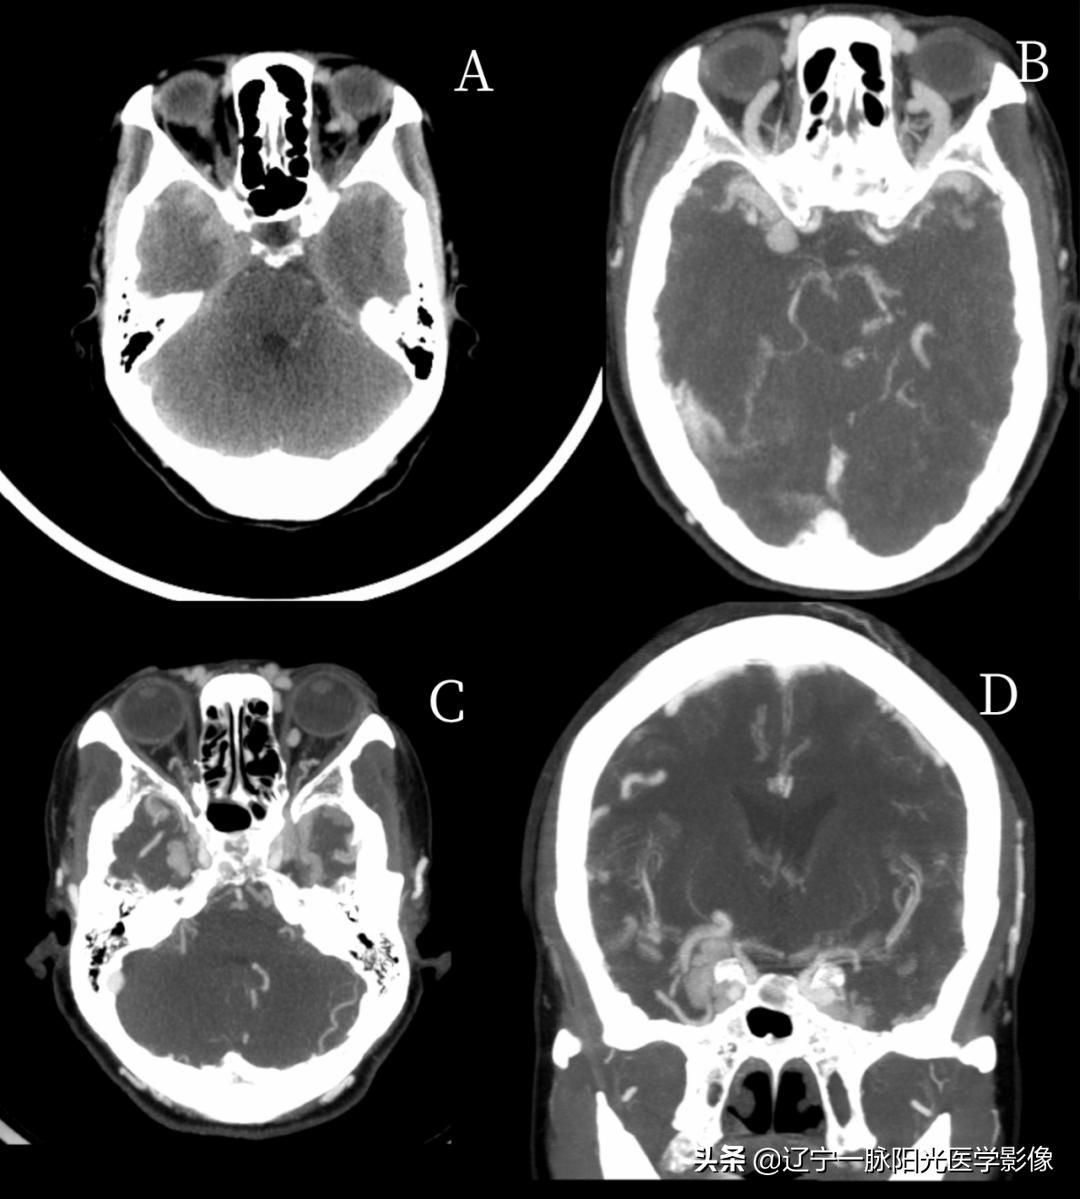

影像所见:

图 A 平扫轴位示双侧海绵窦区见斑片状高密度影

图 B 增强轴位示双侧眼静脉增粗,密度增高

图 C、D 增强轴位示矢状位示海绵窦提前显影,双侧海绵窦呈蚓状、迂曲状增粗,双侧眼静脉扩张增粗

最终诊断:双侧颈内动脉-海绵窦瘘